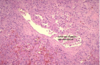

DM T1